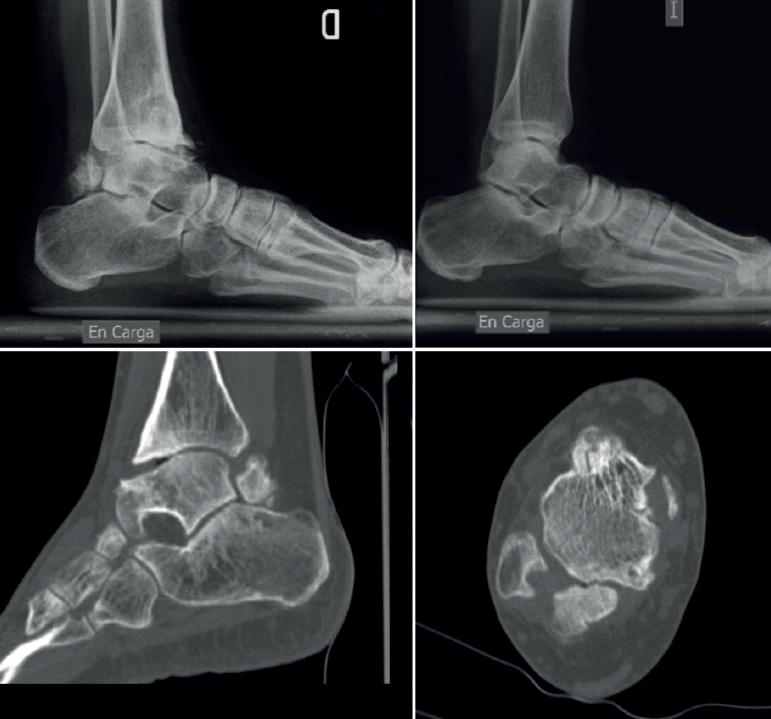

Se presentaría como una segmentación del astrágalo en el plano coronal con 2 fragmentos, uno anterior y otro posterior, separados por una hendidura o pseudoartrosis; a diferencia del os trigonum, el fragmento posterior se articula con la faceta articular posterior del calcáneo y en ocasiones también con la cara articular posterior de la tibia, pudiendo alcanzar un tamaño de un tercio o incluso más del volumen total (Figura 3); ambos fragmentos tendrían una estructura histológica similar(10).

Algunos autores lo han relacionado también con una infección neonatal(56). El aspecto radiológico puede aparentar una fractura y así relacionarse con microtraumatismos repetidos en la infancia o inestabilidad(57), aunque su principal característica es la articulación del fragmento posterior con el calcáneo , llegando a formar una prolongación en consola (Figura 8).